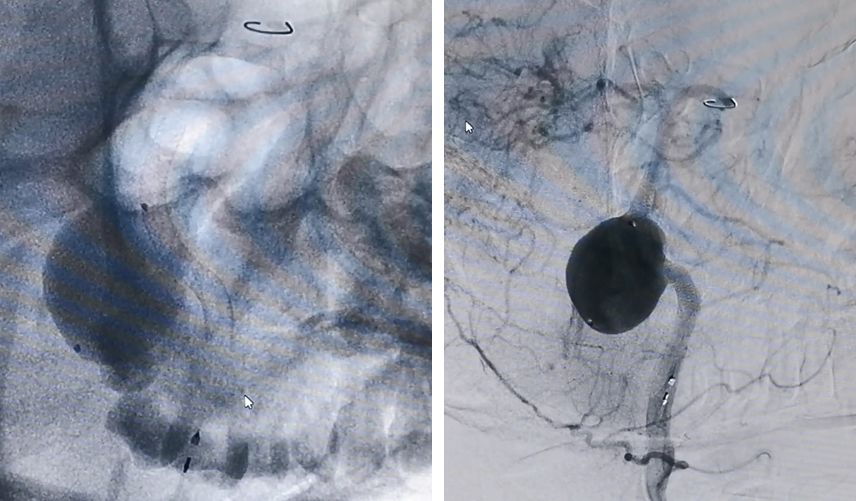

患者核磁共振显示脑桥-延髓前方流空影,考虑动脉瘤,有明显的双腔征,瘤壁有加强,且对脑干有一定的压迫。

2019.5.25外院DSA

通过造影可以看到,动脉瘤主体位于右侧椎动脉,左侧椎动脉也有累及,不过左侧椎动脉PICA以远的部分纤细,考虑可以牺牲掉而不会影响基底动脉血供,但可以部分减少动脉瘤压力。左侧椎动脉为优势椎动脉,则应用PED装置保护并重建之。